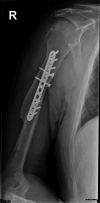

An Upper-Arm Clostridium perfringens Fracture-Related Infection: A Case Report

Fracture-related infections (FRI) pose serious complications, requiring swift surgical intervention. Although C. perfringens infections in FRIs are rare and literature is scarce, this case highlights the successful management and good functional outcome, offering valuable insights for clinicians dealing with such infections.